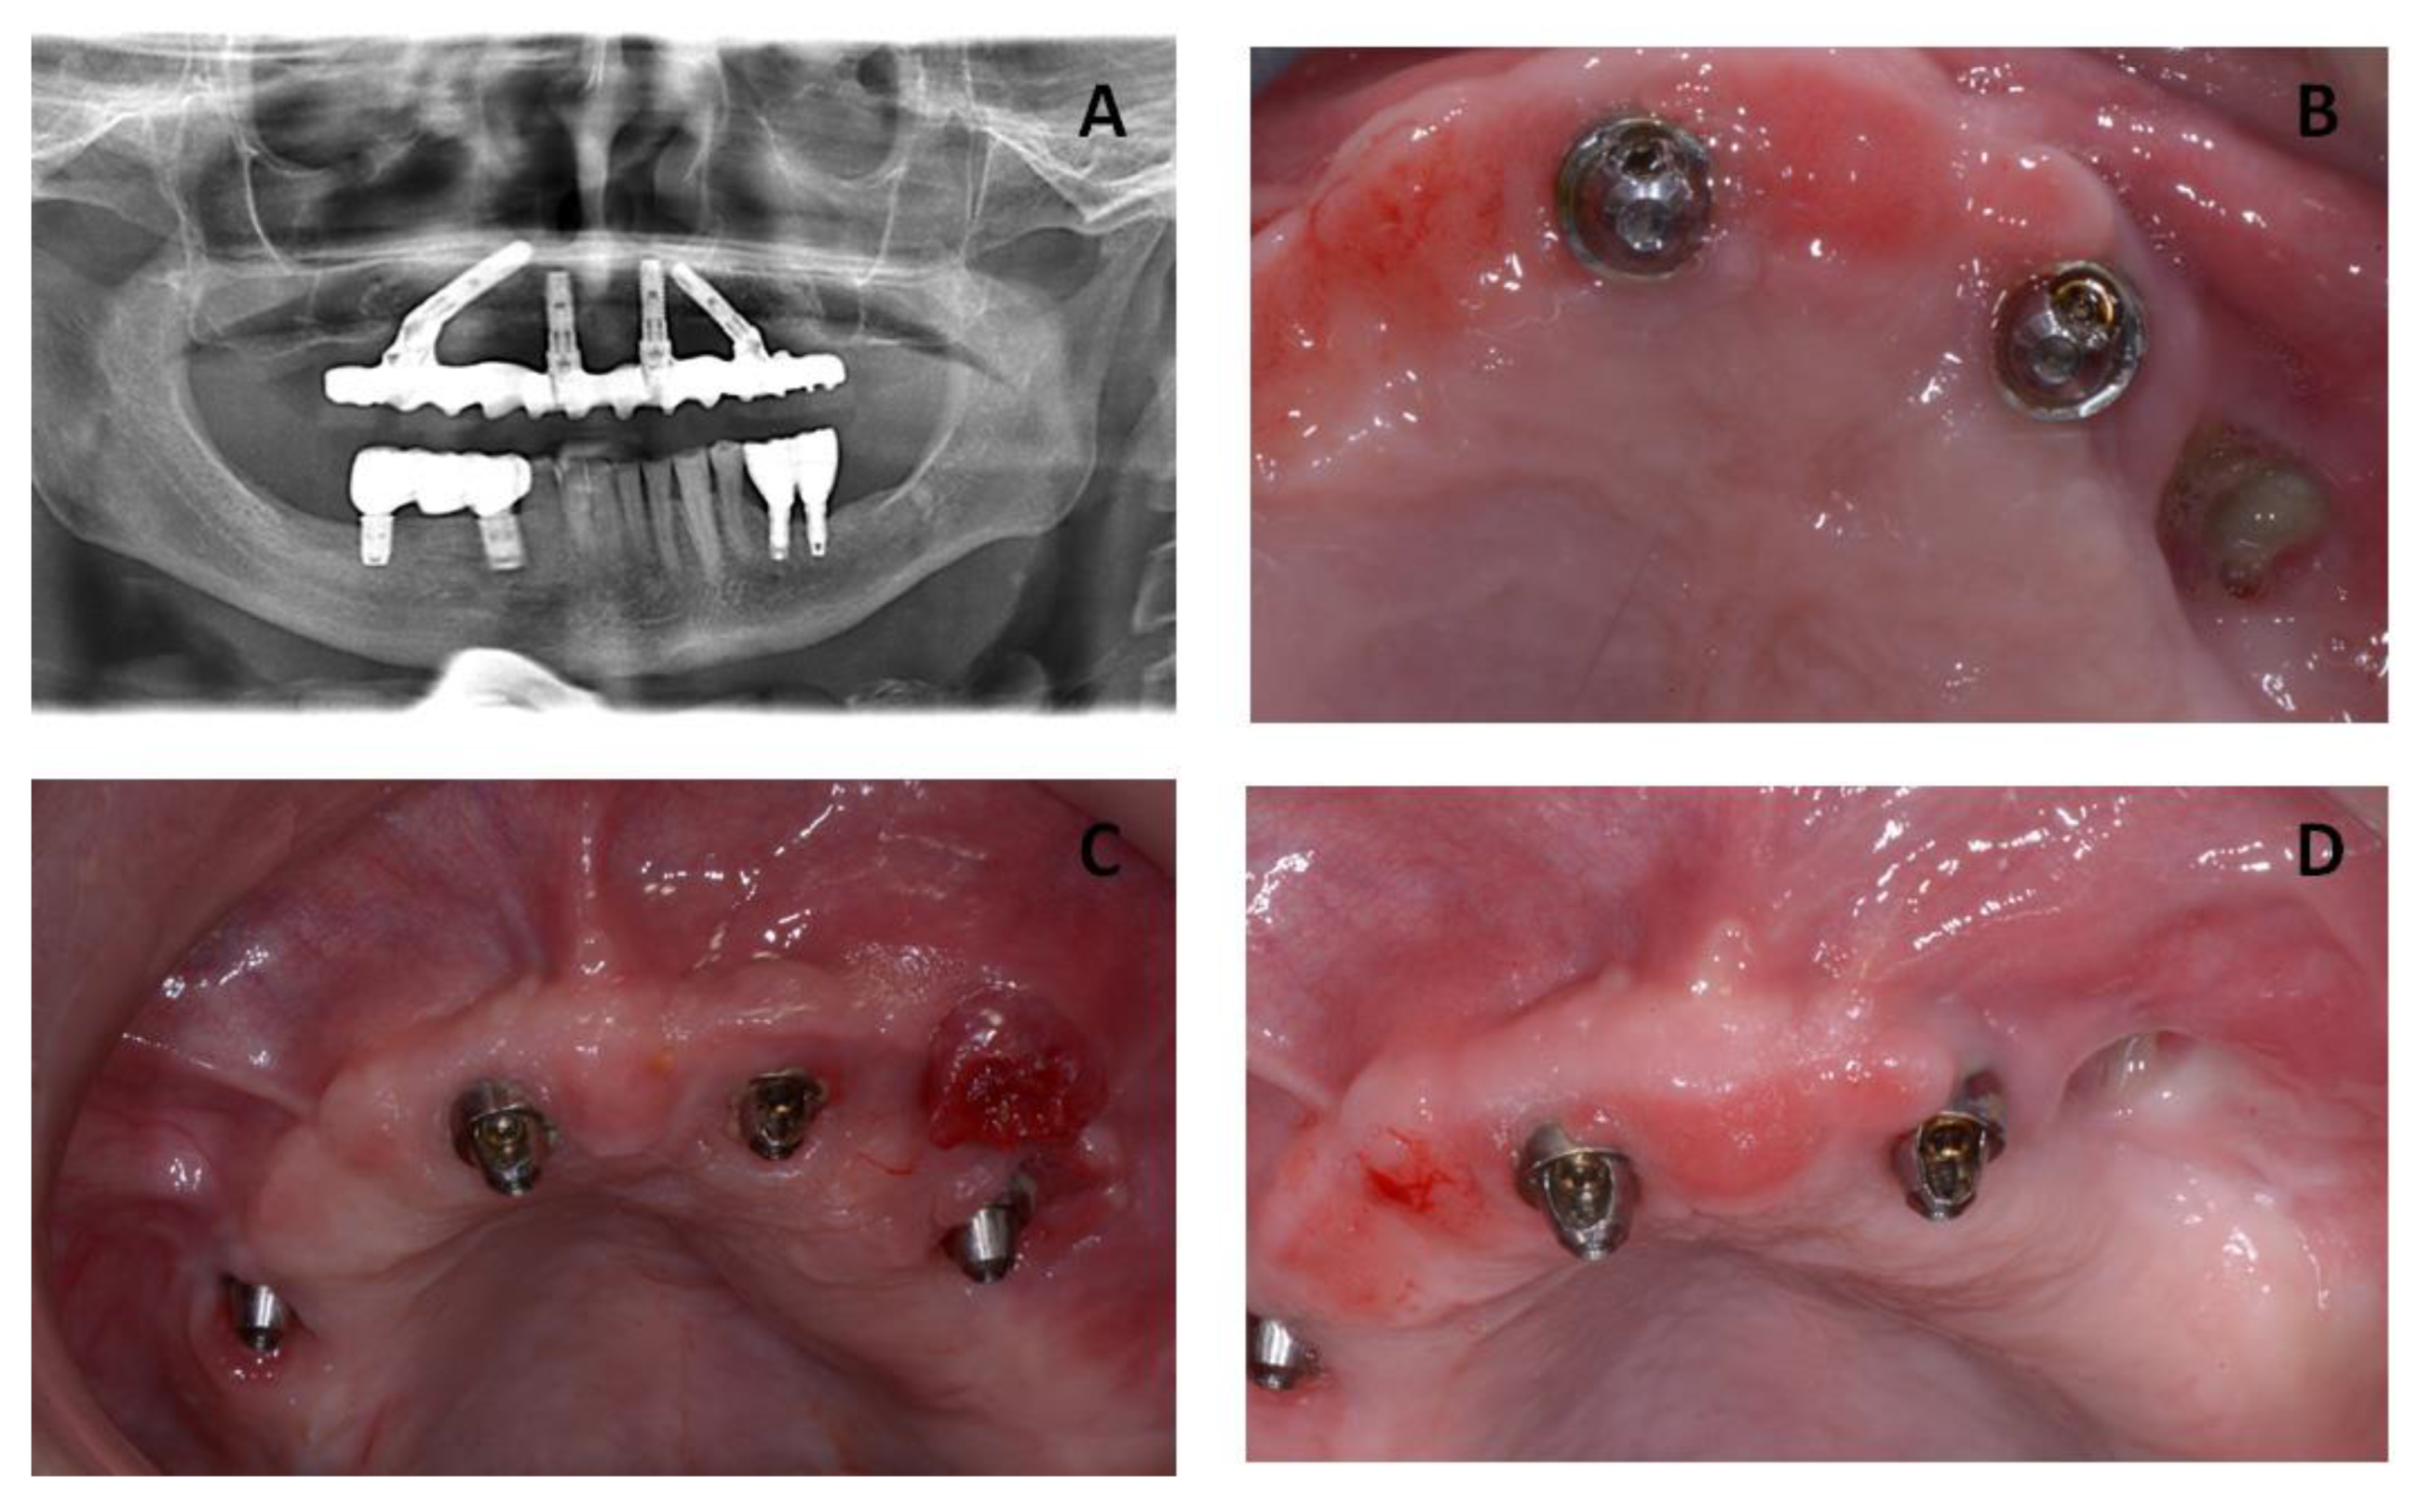

The second surgical session in October 2016 included the removal of implant #46 and the osteonecrosis lesion on the posterior right side of the mandibular bone (Figure 3).

Figure 3. (A) Clinical images from the patient showing a new MRONJ lesion on the posterior right side of the mandibular bone. (B,C) Intra-operative image from the patient showing the removal of the sequester. (D) The radiographic image shows the post-operative situation.